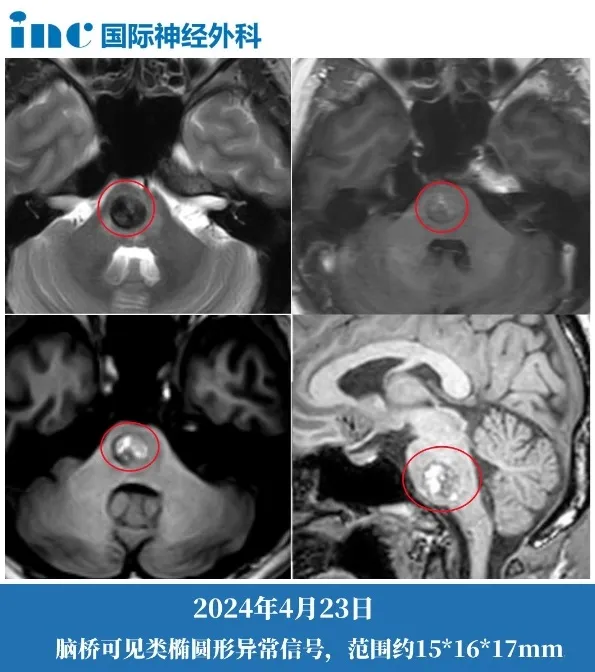

但平静在2024年4月被彻底打破。肢体乏力让他连走路都举步维艰,左侧全身的麻木感逐渐蔓延到面部,复视、耳鸣也接连袭来。复查核磁显示,病灶已经扩大到15×16×17mm,这颗深埋在生命中枢的“不定时炸弹”,正以惊人的速度恶化。